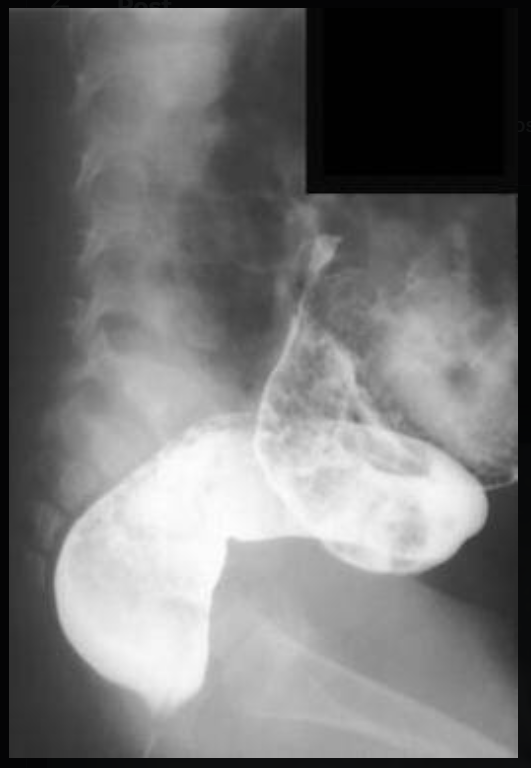

Egy Sanghaj-i fiatalember már évek óta székrekedésre panaszkodott, azonban sokáig nem vette komolyan. Az orvos aki korábban megvizsgálta, azt mondta, hogy egy veleszületett betegségben szenved és nem lehet segíteni rajta. Azt feltételezték róla, hogy úgynevezett megacolon betegségben szenved, amely egy veleszületett vastagbél betegség, aminek lényege, hogy hiányoznak a végbél falában lévő idegvégződések, így a széklelési reflex is hiányzik, emiatt pedig lehetetlen a normális székletürítés.

Még a gyakorlott sebészt is sokkolta annak a látványa, amit kihúzott a beteg férfi gyomrából. Az eltömődött bél hossza 76 centiméteres volt és súlya meghaladta a 13 kilót.